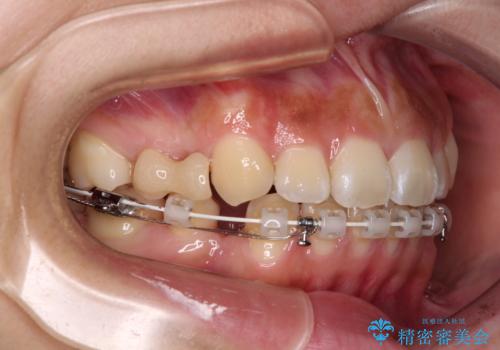

- ハーフリンガル

上下前歯が嘴のように前方に突出しており、唇が閉じにくい状態であったため、上下左右の第一小臼歯4本を抜歯して、口元の突出感を改善することとしました。

目立たない装置を希望とのことで、上顎が裏側、下顎が表側のハーフリンガル装置を用いることとしました。